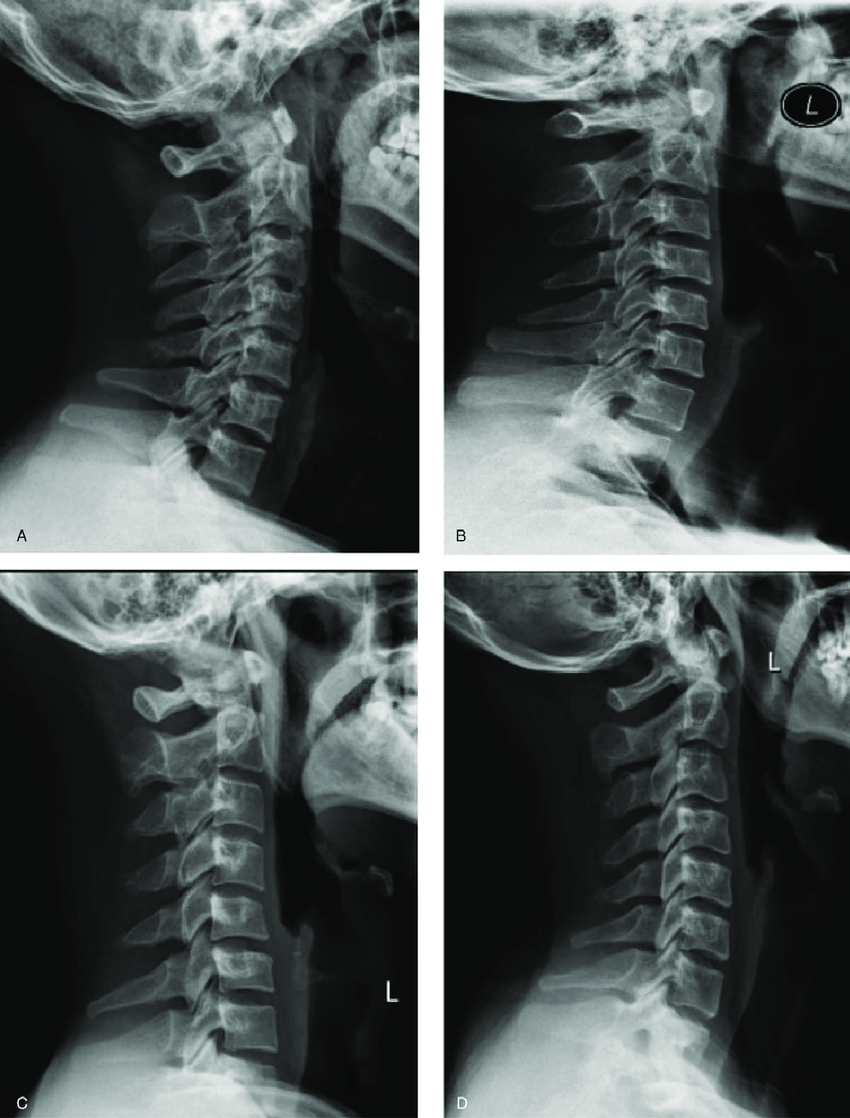

정상적인 경추는 C자 곡선을 이루어 머리 무게를 분산시킵니다. 그러나 거북목·일자목이 되면 머리가 앞으로 빠지면서 경추는 역학적으로 2~3배 무거운 하중을 받습니다.

- 사무직 직장인 A씨: 하루 10시간 컴퓨터 업무 후 뇌검사에서는 이상 없음. 그러나 X-ray상 C커브 소실로 진단 → 물리치료와 운동 후 호전.

- 정확한 진단: MRI·X-ray로 목 구조 확인, 필요시 신경차단술